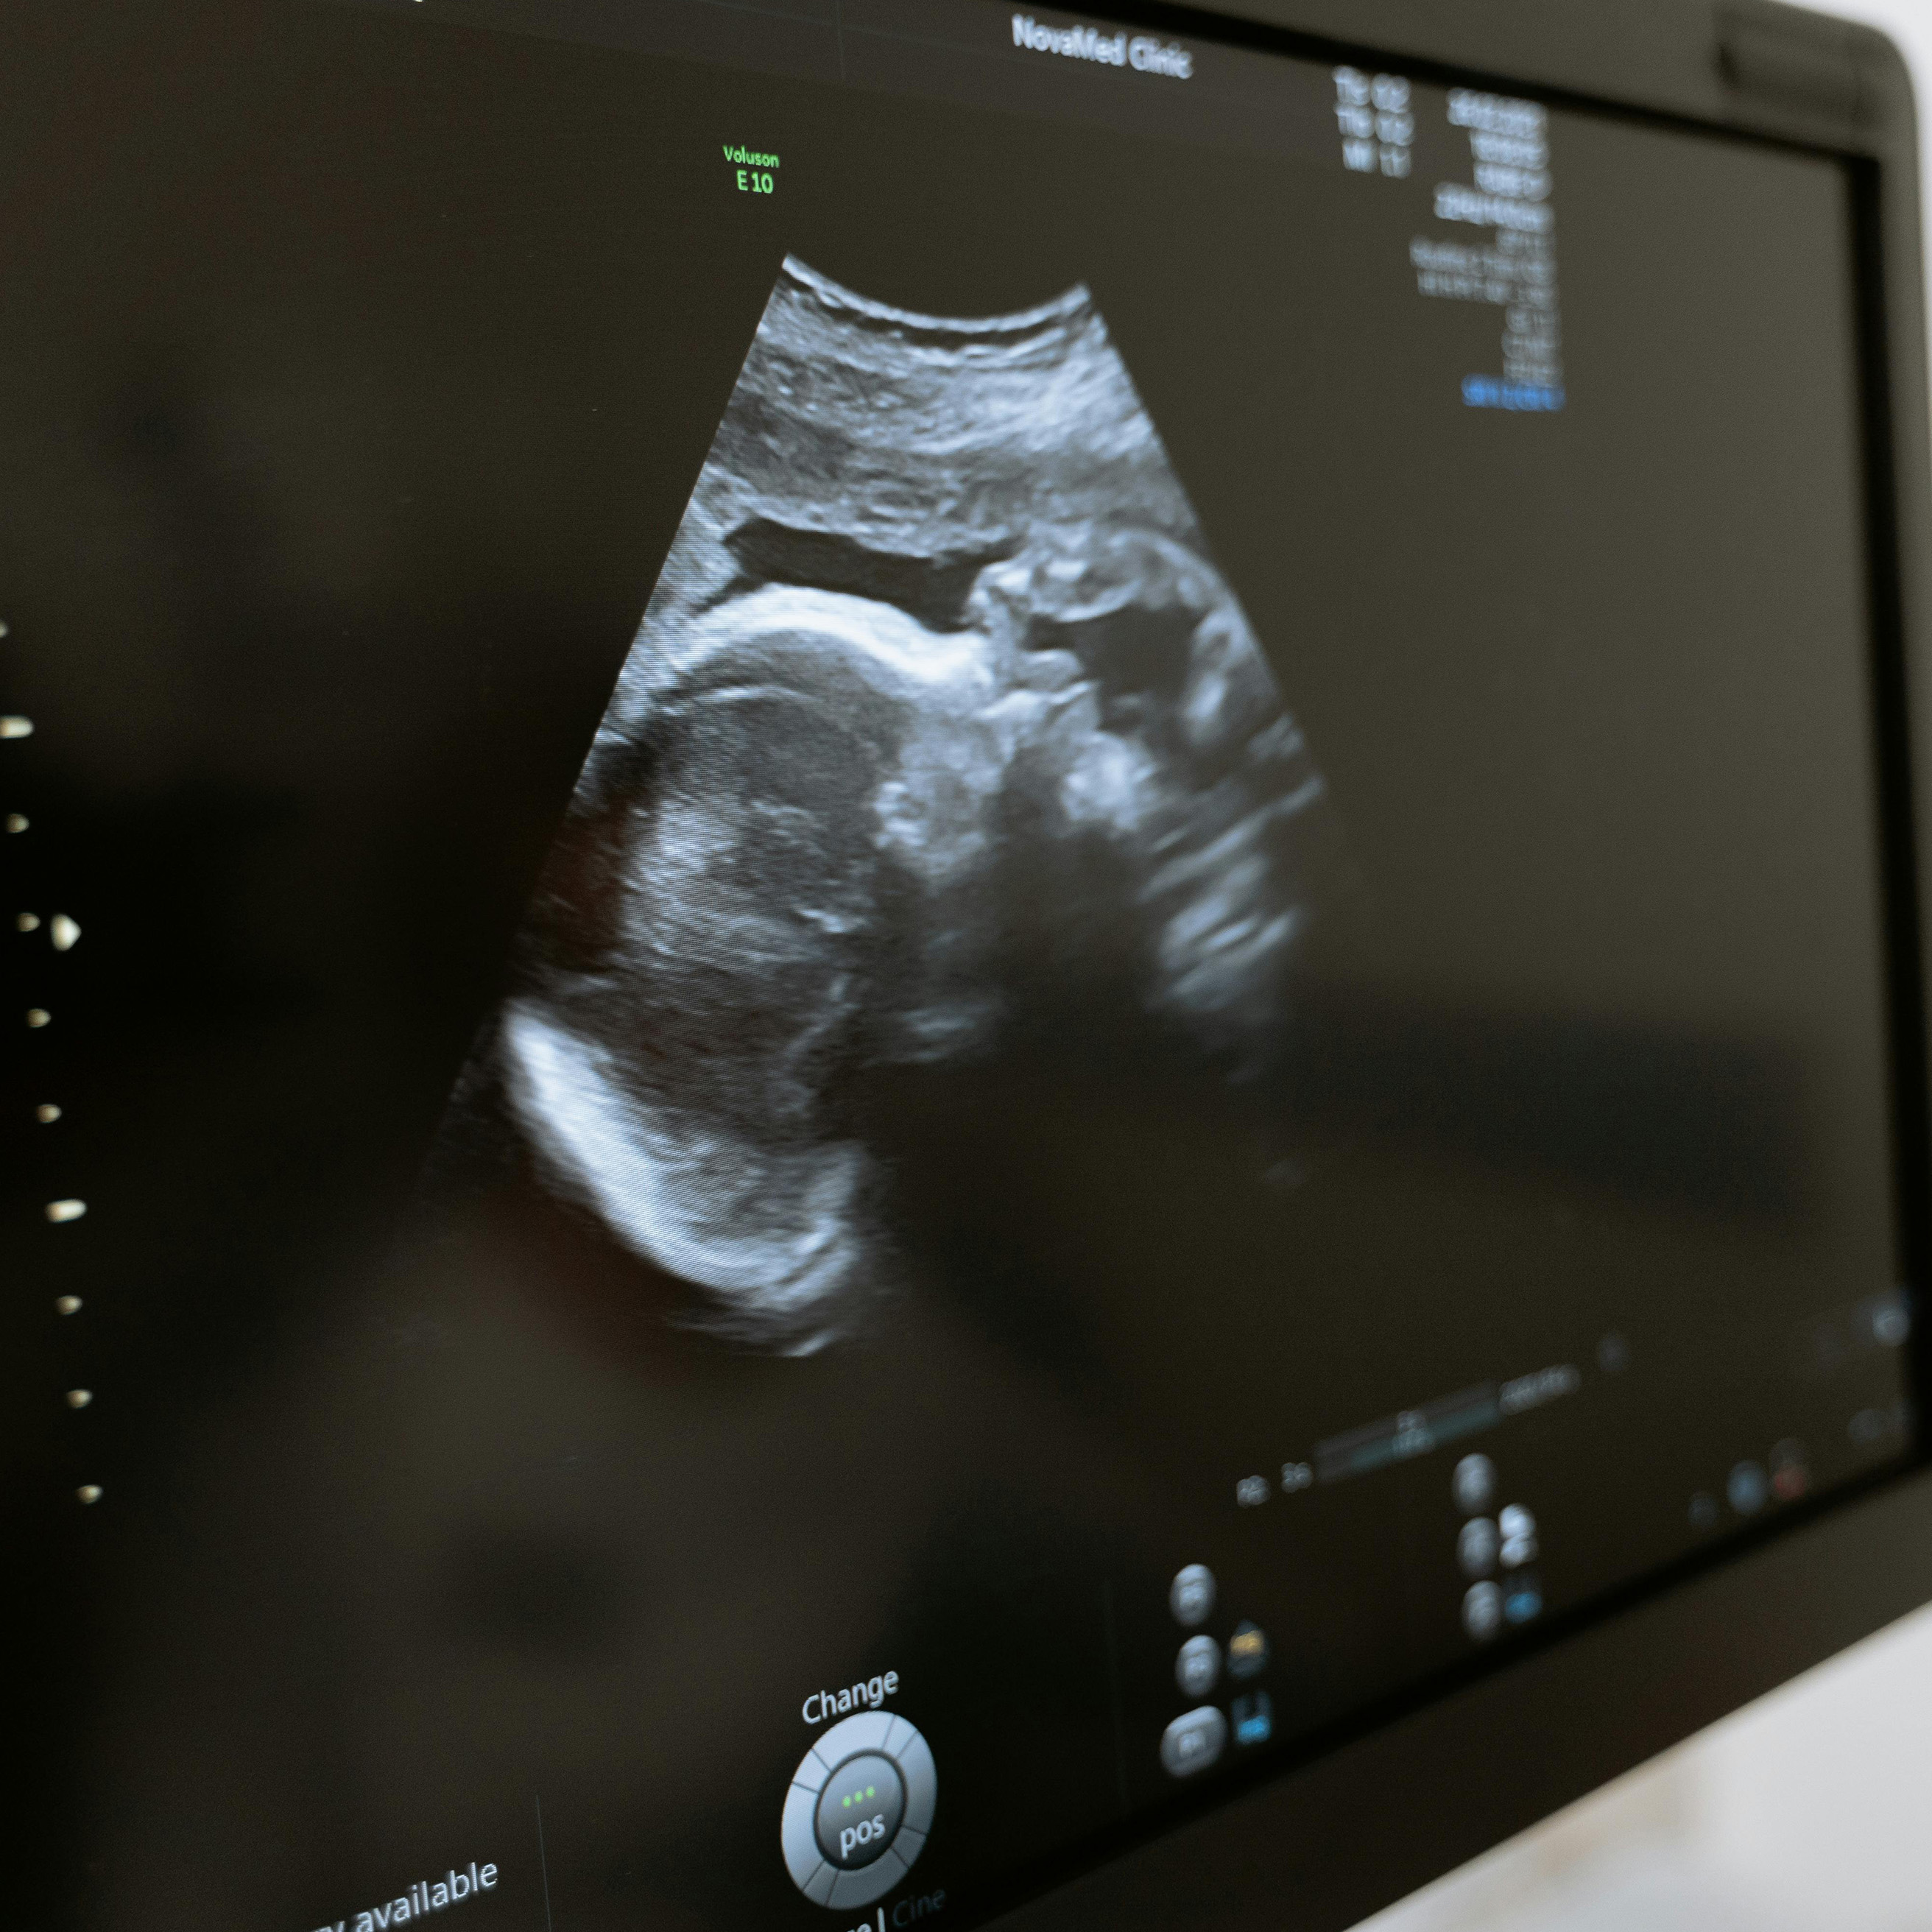

Ecografías Medicina Fetal

• Ecografía Obstétrica

• Ecografía Doppler de Arterias Uterinas

• Ecografía Doppler Fetal

• Ecografía Doppler Placentaria